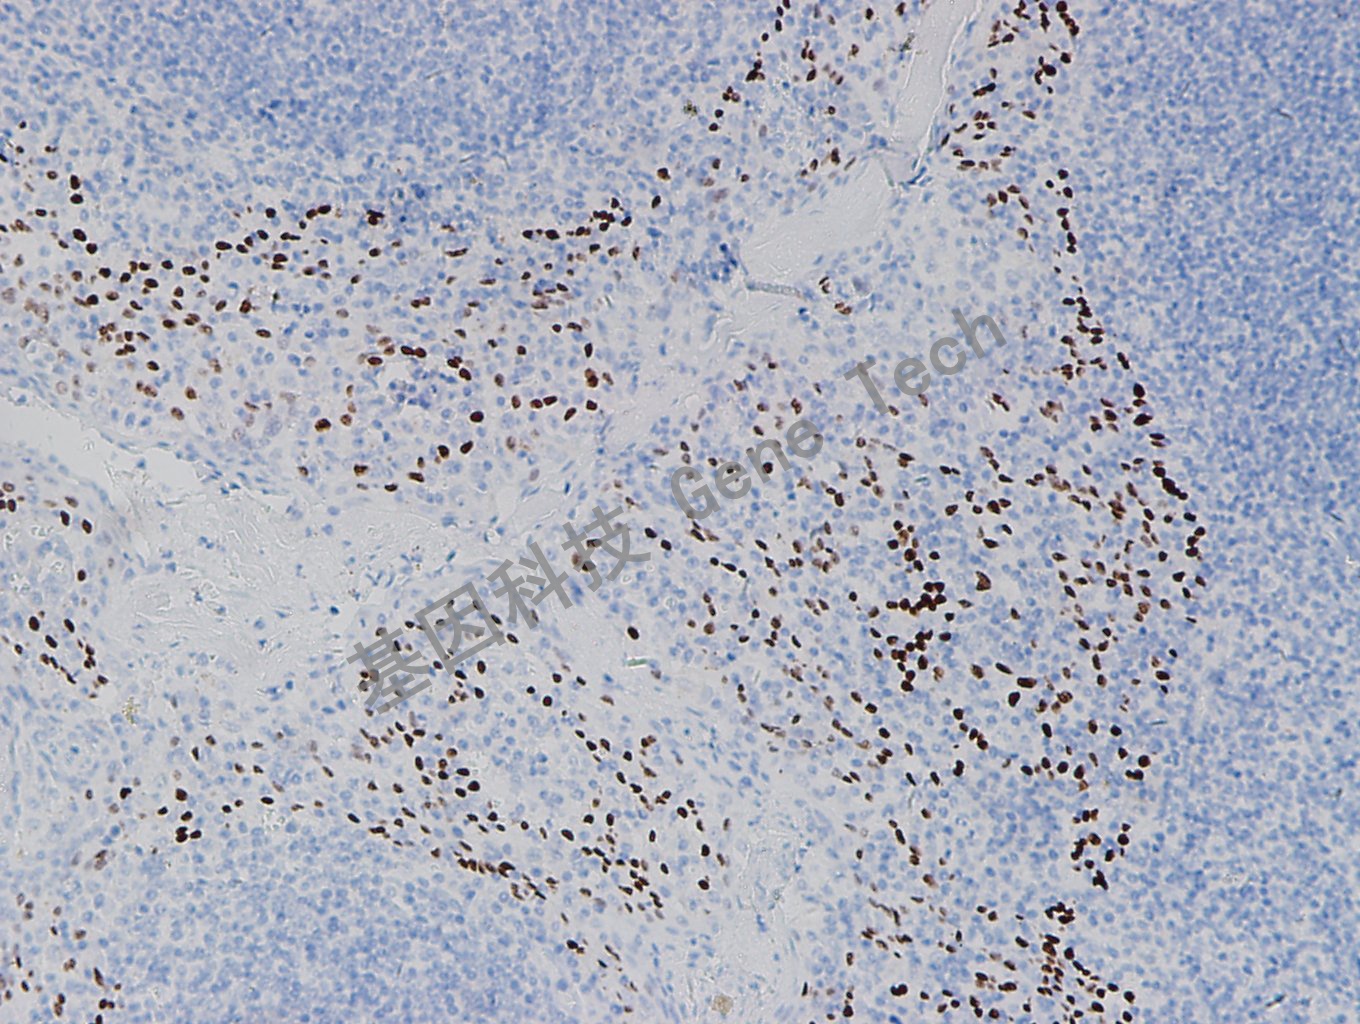

| 預(yù)處理:高pH熱修復(fù) | 陽性部位:細胞核 | 陽性對照:肺麟癌 |

| 扁桃體石蠟切片,用 p40(GR006)染色,細胞核陽性,DAB 顯色。 | ||